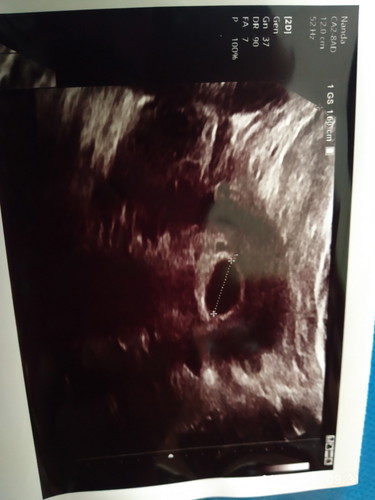

Siang bunda-bunda hebat di sini ... Maaf mau tnya dan berbagii cerita yuk .. Khan cerita nya saya mei kemaren keguguran , dan alhamdulillah ini insha allah isi lagi ... Mau tnya utk bisa dpat anak perempuan gimana yaa bun ... Makasiih🙏🏻🙏🏻🙏🏻#jangandibully #Nanya #theAsianparentIndonesia #seriusnanya #bantusharing